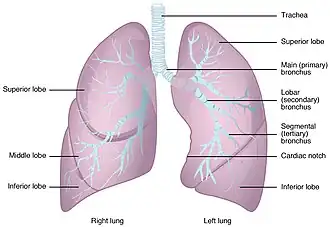

Anatomic resections

Anatomic resections refer to procedures where a section of the lung is removed with respect to lobar or segmental anatomy.[20] These include pneumonectomies, lobectomies and segmentectomies and are commonly used for the treatment of NSCLC. Preoperative evaluations for resections include cancer staging via a chest CT scan and PET scan, followed by assessments of pulmonary reserve volume and cardiac function to determine the amount of lung tissue that can be safely removed without developing pulmonary insufficiency.[21] Following tissue removal, the resultant bronchial stumps are pressurised under water to check for air leaks before the resection is deemed complete.[22]

Lobectomy

A lobectomy is the surgical removal of one of the five lung lobes (right upper, right middle, right lower, left upper and left lower lobes).[24] Lobectomies are the most common type of lung surgery and the standard operation for most NSCLC patients.[25] Though specific surgical techniques vary for each lobe, the general workflow is identical. The lobe to be resected is first visualized through thoracotomy or thoracoscopy. Next, the surrounding lymph nodes are harvested to check for metastasis. After confirmation that no metastasis has taken place, the vasculature of the lobe is controlled by blood vessel division using a stapler. Stapling is also used to divide the lobar bronchus and subsequently separate the lobe along the lung fissure(s). After the lobe is removed, lymph node dissection is completed.

Specific considerations exist for certain lobes. Right middle lobectomies are not usually carried out alone and are instead part of a bilobectomy alongside a right upper or lower lobectomy. Left upper lobectomies require additional caution to avoid arterial branches from the fissure and proximal pulmonary artery.[21] Another risk is the proximity of the recurrent laryngeal nerve to the upper mediastinal lymph nodes, which increases its risk of injury during lymph node dissection.[26] Thus, a swallowing study is required if nerve damage is suspected postoperatively.[13]

Sleeve lobectomy

Segmentectomy